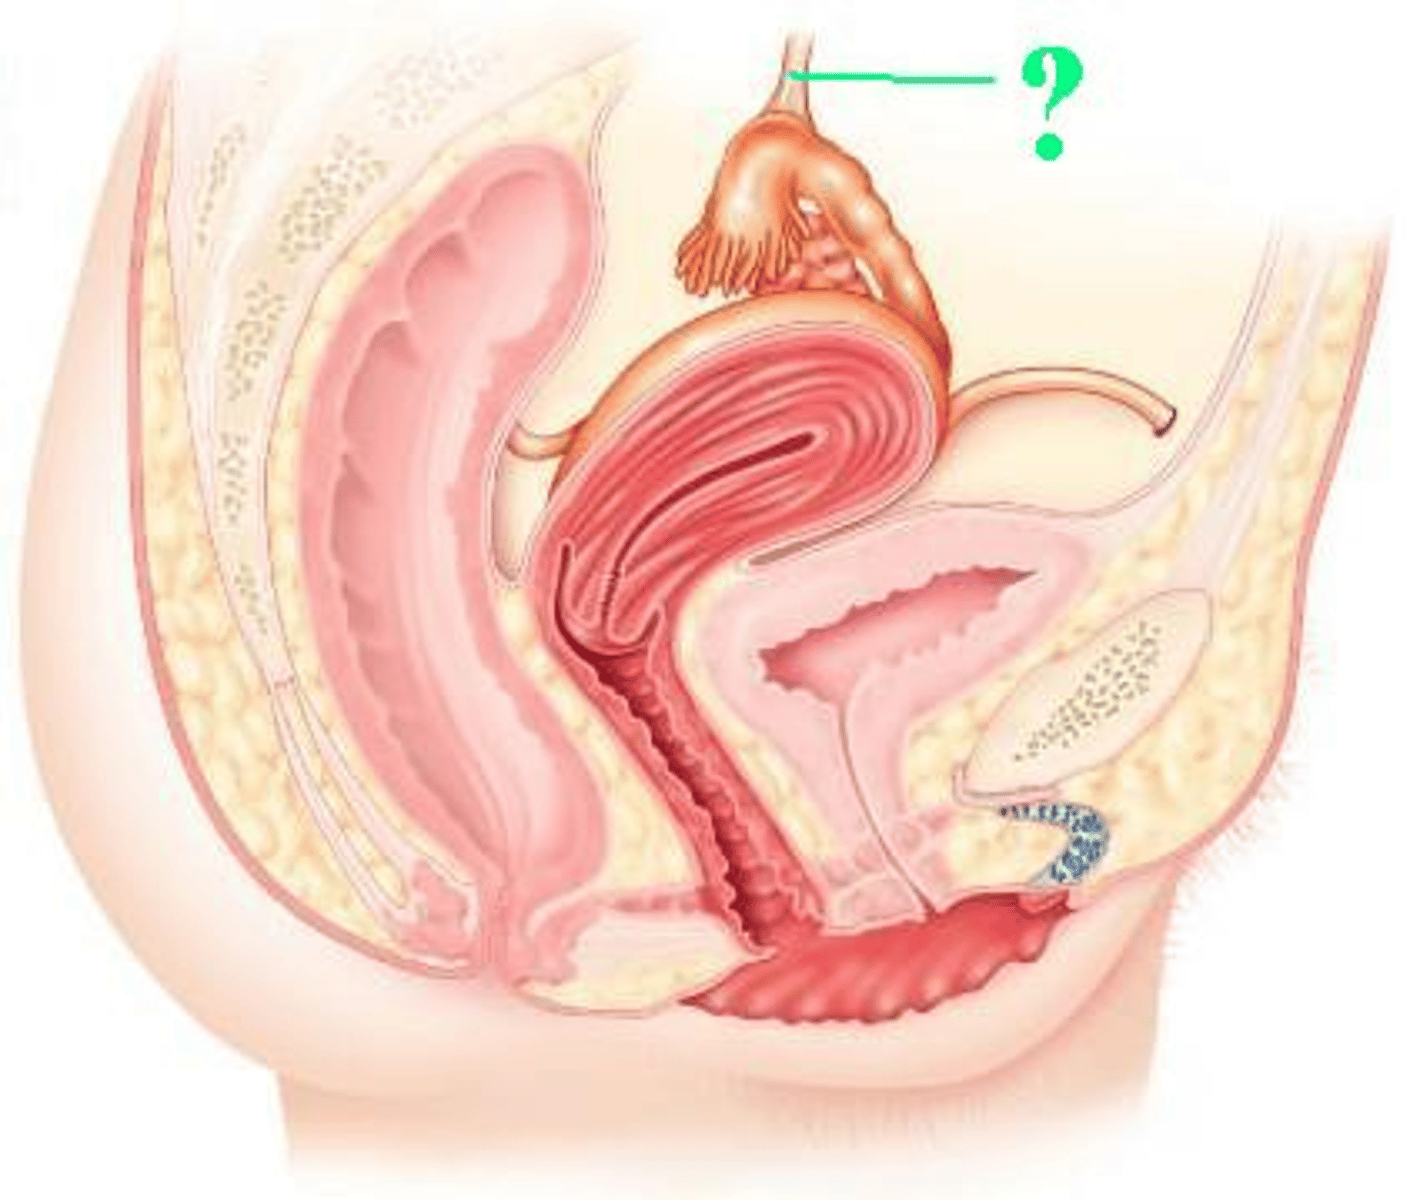

fimbriae

Identify the indicated structures.